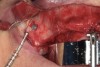

In the maxilla, the two distal implants placed in the posterior region are tilted anterior to the maxillary antrum, normally at an angle of 30° to 45° (Figure 2). In the mandible, position the implants anterior to the mental foramen and insert them at an angle of 30° to 45°. Place the All-on-4 surgical guide into a 2-mm osteotomy made in the midline position of the maxilla or mandible, and contour the titanium band to follow the arc of the opposing arch (Figure 3). Alternatively, a conventional surgical guide can be used. Use the vertical lines on the guide as a reference for drilling at the correct angulation (≤ 45°). The implant chosen should have a design and osseoconductive surface appropriate for ensuring sufficient primary stability for immediate function. A manual torque wrench is used to check the final torque, which should attain 35 Ncm to allow immediate function.

Fig 2. Placement of maxillary implants with two distal implants in the posterior region tilted anterior to the

maxillary antrum. A lateral window was made to visualize the anterior border of the antrum.